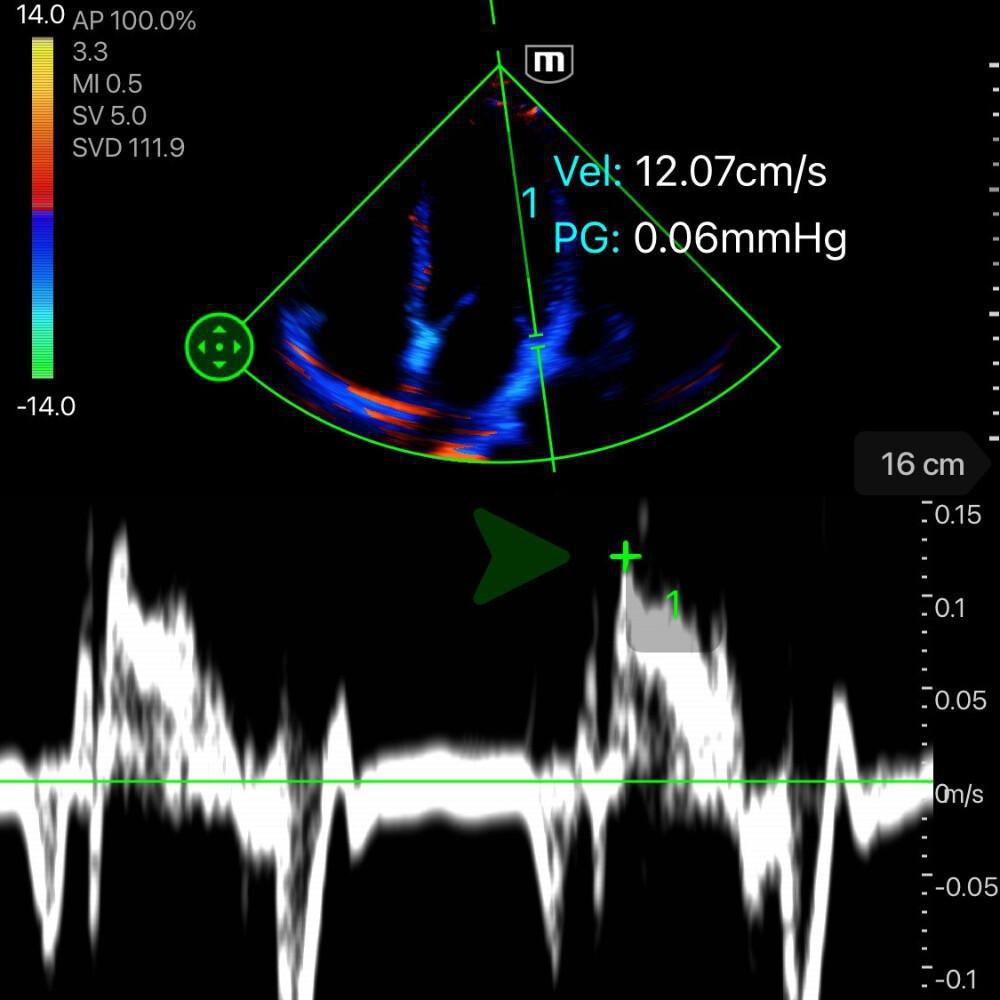

🧮 Calcul de l'onde S'

L’onde S’ mesurée en Doppler Tissulaire (TDI) au niveau de l’anneau mitral permet une evaluation indirecte de la FEVG avec une corrélation satisfaisante.

Comment mesurer l’onde S’

-

Vue apicale 4 cavités.

Activer le Doppler Tissulaire (TDI).

Placer le curseur sur l’anneau mitral latéral.

Identifier et mesurer le pic de l’onde S’ (vélocité systolique).

Interprétation

S’ < 8 cm/s → dysfonction systolique du VG.

S’ 8-10 cm/s → fonction réduite ou zone grise.

S’ > 10 cm/s → fonction systolique généralement conservée.

![]()